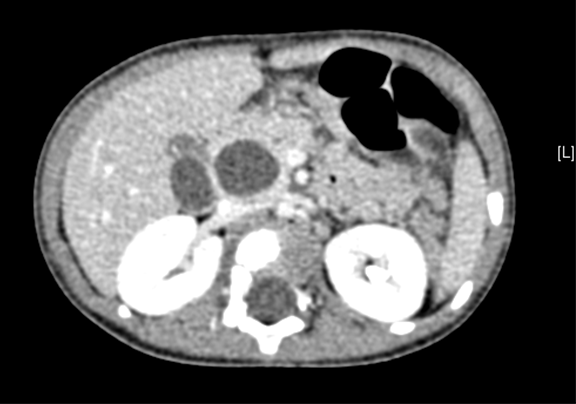

上腹部动态三维成像(增强)CT:诊断意见:符合胆总管囊肿胆囊炎可能性大。

术前CT检查:

动脉期